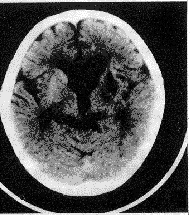

1.CT MRI檢查 腦室系統擴大並尤以側腦室前角為著;側腦室周圍特別是額角部有明顯的間質性水腫帶;腦室擴大的程度甚於腦池的擴大;腦回無萎縮表現 腦溝不加寬。不過,需要與腦萎縮相鑑別,因為嚴重腦挫傷、軸突損傷、腦缺血 缺氧和壞死等造成的腦萎縮也具有腦室擴大的CT影像。後者的特點是:側腦室普遍擴大 腦溝增寬、無腦室周圍的透亮水腫區。MRI檢查雖與CT所見相同,但更為明確和清晰:首先是側腦室前角的擴張及腦室周圍的間質性水腫帶,可於T2加權圖像上顯示出明顯的高信號;其次於冠狀面可以測出兩側室頂之間的夾角小於120°,相反在腦萎縮病人此角則常大於140°;再者於矢狀面尚可看到第三腦室呈球形擴大,視隱窩和漏斗隱窩變淺變鈍,而在腦萎縮病人,其第三腦室前後壁、漏斗隱窩、視隱窩則無明顯變形,雖有擴大但仍保持其原有輪廓。